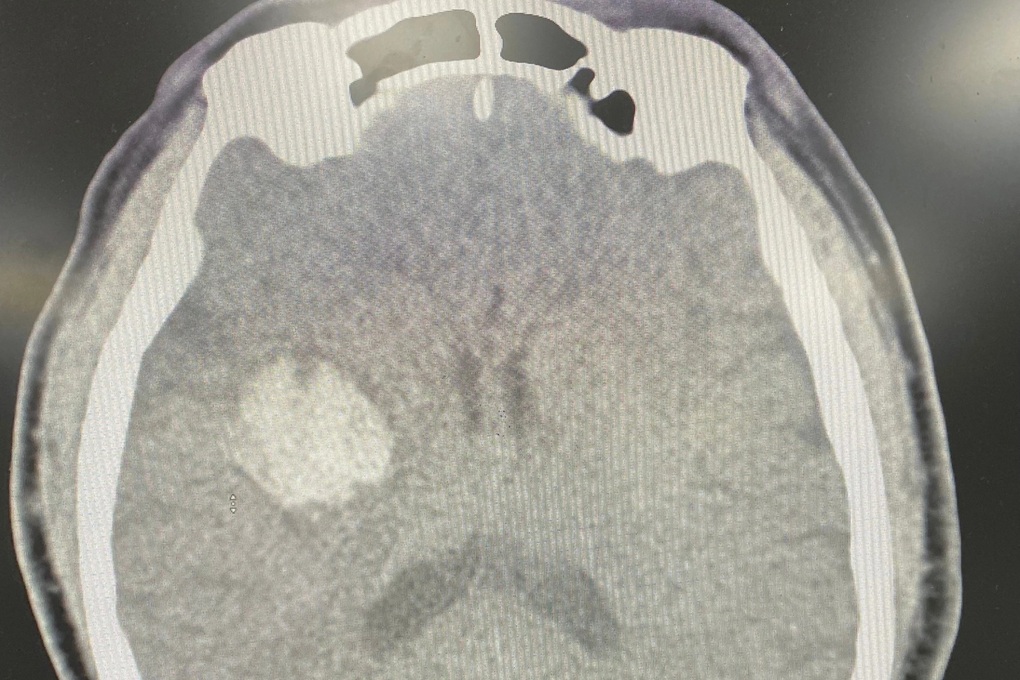

Bệnh nhân được đưa vào cấp cứu tại Bệnh viện Trung ương Quân đội 108. Ảnh: Bác sĩ cung cấp

Bác sĩ Phạm Duy Hoàng, Khoa Cấp cứu, cho biết kết quả chụp cắt lớp vi tính sọ não dựng hình mạch máu não cho thấy hình ảnh xuất huyết não vùng nhân xám trung ương phải, không có bất thường mạch máu não.